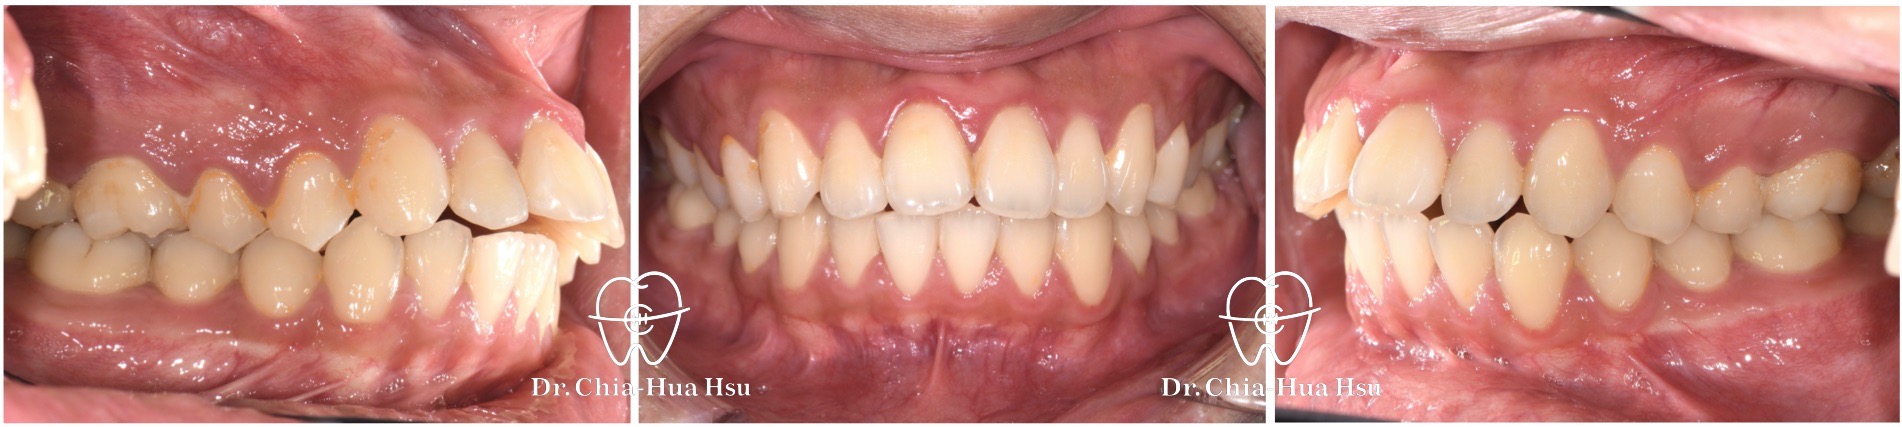

- 風趣幽默的20歲黃同學因為暴牙來院求診,由於患者下巴後縮又暴牙屬於複雜困難病例,還好病人十分配合療程,在許醫師悉心治療下,經歷兩年左右,讓治療順利完成。

- 病患主訴:暴牙、嘴凸、中線歪斜。

- 問題分析:患者是嚴重的骨骼二類咬合(Skeletal Class II)、下巴後縮、暴牙以及齒列不整齊。

- 治療方式:使用傳統金屬矯正器,並拔除四顆小臼齒,配合多支暫時性迷你骨釘來完成治療。

- 治療時間:2 年 2 個月。

- 治療結果:齒列排齊,外觀明顯改善,笑容更自信。

治療前

治療後